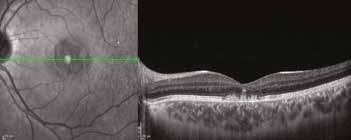

Milano nel 2017. Nel maggio del 2023 inoltre, sempre al medesimo congresso, il Dottor Alfredo Pece mi ha nuovamente invitato a mostrare un caso analogo, ma ancora più esemplificativo, in quanto ottenuto in un giovanissimo paziente affetto da Maculopatia vitelliforme giovanile di Best, in cui i primi 5 aa di assenza di terapia mostravano un significativo peggioramento visivo da 10/10 bilaterale a 6-7/10 in OD e 7/10 in OS con iniziale comparsa di metamorfopsie e segni di iniziale sofferenza neuro-recettoriale. Nel follow-up successivo all’introduzione di DHA al-

gale (OMEGAL DHA capsule softgel) con aggiunta di un complesso antiossidante contenente curcuma MERIVA ®, luteina, zeaxantina, vitamine c, e, d3, rame e zinco si osservava un’eclatante risposta progressiva nei successivi 18 mesi in OS e 24 mesi in OD in termini di completo riassorbimento dell’accumulo lipofuscinico maculare, notoriamente tossico per l’EPR, senza significativa evoluzione atrofica e miglioramento significativo delle linee IS-OS recettoriali in entrambi gli occhi e della qualità visiva e QoL del paziente con BCVA finale di 9/10 in OD e 9-10/10 in OS.

Il lungo follow up del paziente durato 5 anni in assenza di cura integrativa continuativa se non saltuario uso di formula ared2 per brevi cicli mostra un significativo peggioramento anatomico strumentale OCT e funzionale del paziente con evoluzione dallo stadio 1 allo stadio II/III e solo dopo uso concomitante di DHA algale OMEGAL DHA ed un Complesso antiox si osservava una eclatante ed imprevedibile risposta, nei successivi 18 mesi in occhio sinistro e 24 mesi in OD, con completo riassorbimento del voluminoso accumulo lipofuscinico senza significativa evoluzione atrofica. Dopo inizio della cura invece si osserva un miglioramento significativo e duraturo dell’aspetto delle linee recettoriali e conseguentemente della qualità visiva in entrambi gli occhi, con un significativo miglioramento della qualità di vita del giovane paziente.

Sopra, miglioramento progressivo dopo cura.